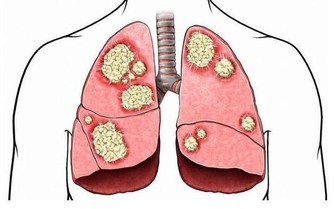

事實上,包括胃癌、宮頸癌、肝癌、肺癌等,常在晚期被發現。為什麼會發生這些?

此外,更可怕的是,許多類型的癌症正在迅速發展,並可以在短短幾個月內發展到晚期,擴散和轉移。

肝癌

有句話說:“胃是角,肝是啞的”,胃粘膜神經分佈很廣,一旦潰瘍和胃酸大,就很容易感覺到。

然而,肝臟中沒有疼痛神經。

只有當肝被癌細胞破壞時,才會引起腫脹、硬化、腹水,並伴有疼痛神經觸及肝細胞膜。

然後它會保持警惕。同時,多為肝癌晚期。